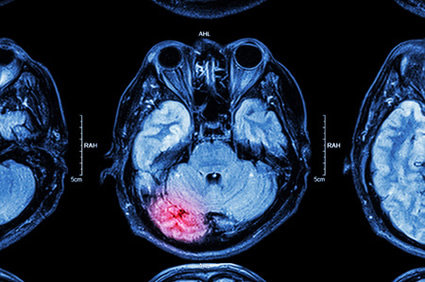

O acidente vascular cerebral (AVC), popularmente conhecido como derrame cerebral, é a doença neurológica que mais frequentemente acomete o sistema nervoso e é a principal causa de incapacidades físicas e mentais. Ele ocorre quando o suprimento de sangue para uma parte do cérebro é interrompido subitamente (AVC isquêmico) ou quando um vaso sanguíneo no cérebro rompe, extravasando seu conteúdo e dando origem a um hematoma, ou coágulo, que provoca sofrimento no tecido cerebral (AVC hemorrágico). O AVC isquêmico é o mais comum, representa cerca de 85% dos casos de derrames. Já o AVC hemorrágico, embora menos comum, apresenta maior mortalidade.

2. Hemorrágico, caracterizado por sangramento dentro do tecido cerebral, devido ao rompimento de um vaso sanguíneo.

Alguns dos sinais e sintomas do AVC podem aparecer também em outras condições que levam a um déficit neurológico focal. Muitos destes outros diagnósticos podem ser esclarecidos com um exame de glicemia ou com exames de imagem como tomografia computadorizada ou ressonância nuclear magnética do crânio.